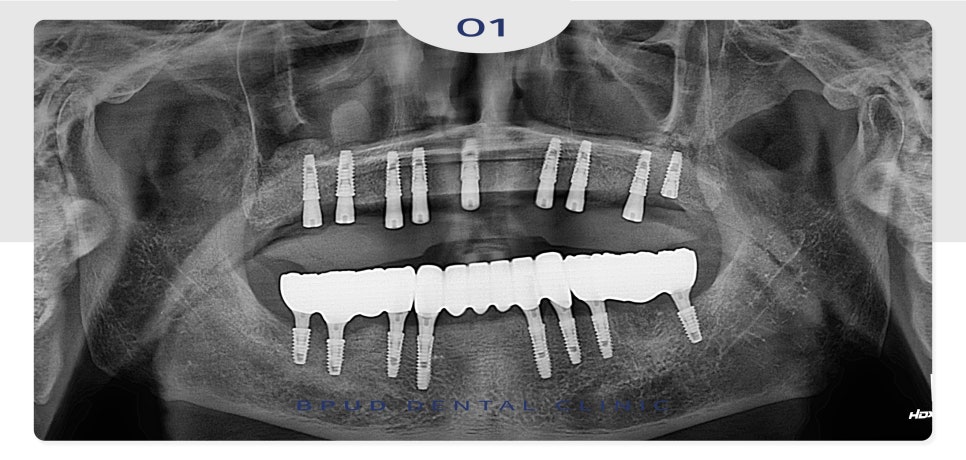

24.09.21

식립 후 임시 틀니를 제작해 드렸으며

아래쪽은 약 3개월 후

최종 보철물을 완성하였습니다.

25.01.16

위쪽은 난이도가 높은 상악동 거상술을

시행하였으므로 1개월 정도 더 기다려준 뒤

최종 보철까지 마무리하였습니다.